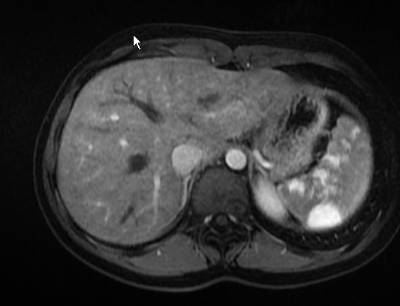

МРТ

Использование контрастного вещества помогает более точно оценить опухоль, а также дифференцировать ее именно в гемангиому. С помощью МРТ можно не только составить прогноз на лечение и выздоровление, но и предположить, почему опухоль сформировалась именно в селезенке и какие факторы этому способствовали.

Магнитно-резонансная томография, также как и компьютерная томография, на сегодняшний день является наиболее точной диагностической процедурой, позволяя выявлять даже опухоли начальных стадий, диаметр которых едва достигает 3,5 мм. Недостатком процедуры является ее относительно высокая стоимость, а также наличие некоторых противопоказаний.

Компьютерная томография

С помощью этого метода исследования есть возможность оценить состояние опухоли, ее прогрессирование и тип. Процедура схожа с МРТ, однако методика КТ базируется на воздействии рентгеновских лучей, при правильном направлении и кольцевании которых получается трехмерное изображение исследуемой области тела.